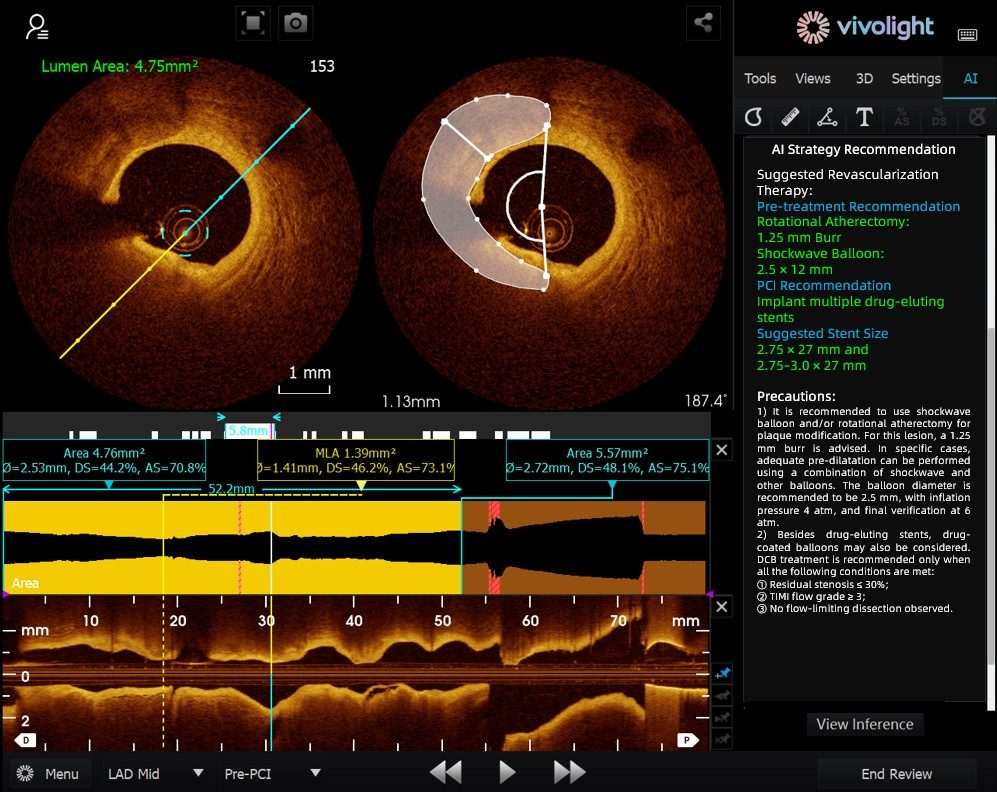

Desarrollado a partir del sistema OCT de Vivolight Medical, el AI-OCT es un sistema inteligente de apoyo a la decisión de última generación para imágenes intravasculares. Integra datos diagnósticos de imágenes intravasculares dispersos —como el diámetro luminal, las lesiones causantes, la OCT-FFR y las características de la placa— en estrategias de tratamiento integrales y recomendaciones prácticas. Como software de investigación independiente integrado en la plataforma OCT, se desarrolla en colaboración con diversos hospitales para crear versiones personalizadas que se adapten a necesidades clínicas específicas.

Durante el foro de vanguardia, los expertos destacaron que el sistema AI-OCT representa un cambio transformador, pasando de la mera visualización de imágenes a la elaboración de planes de tratamiento, lo que permite abordar los desafíos de la sobrecarga de información y la compleja toma de decisiones en los procedimientos de intervención cardíaca, que tradicionalmente dependen en gran medida de la experiencia del médico. Entre las principales ventajas del sistema se incluyen:

●Guía intraoperatoria en tiempo real: Organiza de forma dinámica la información diagnóstica durante la cirugía, proporcionando métricas clave y recomendaciones clínicas.

●Toma de decisiones basada en la evidencia: Todas las sugerencias se ajustan al consenso de expertos y a las guías clínicas, lo que garantiza rigor y fiabilidad.

El sistema AI-OCT adopta una arquitectura de "modelo pequeño + macrodatos + modelo grande": los modelos pequeños permiten una interpretación precisa de las imágenes, mientras que los modelos grandes impulsan un razonamiento clínico integral. Gracias a bases de datos cardiovasculares de alta calidad y a la tecnología de Generación Aumentada por Recuperación (RAG), ofrece soporte integral, desde la evaluación de lesiones hasta el desarrollo de estrategias de tratamiento.